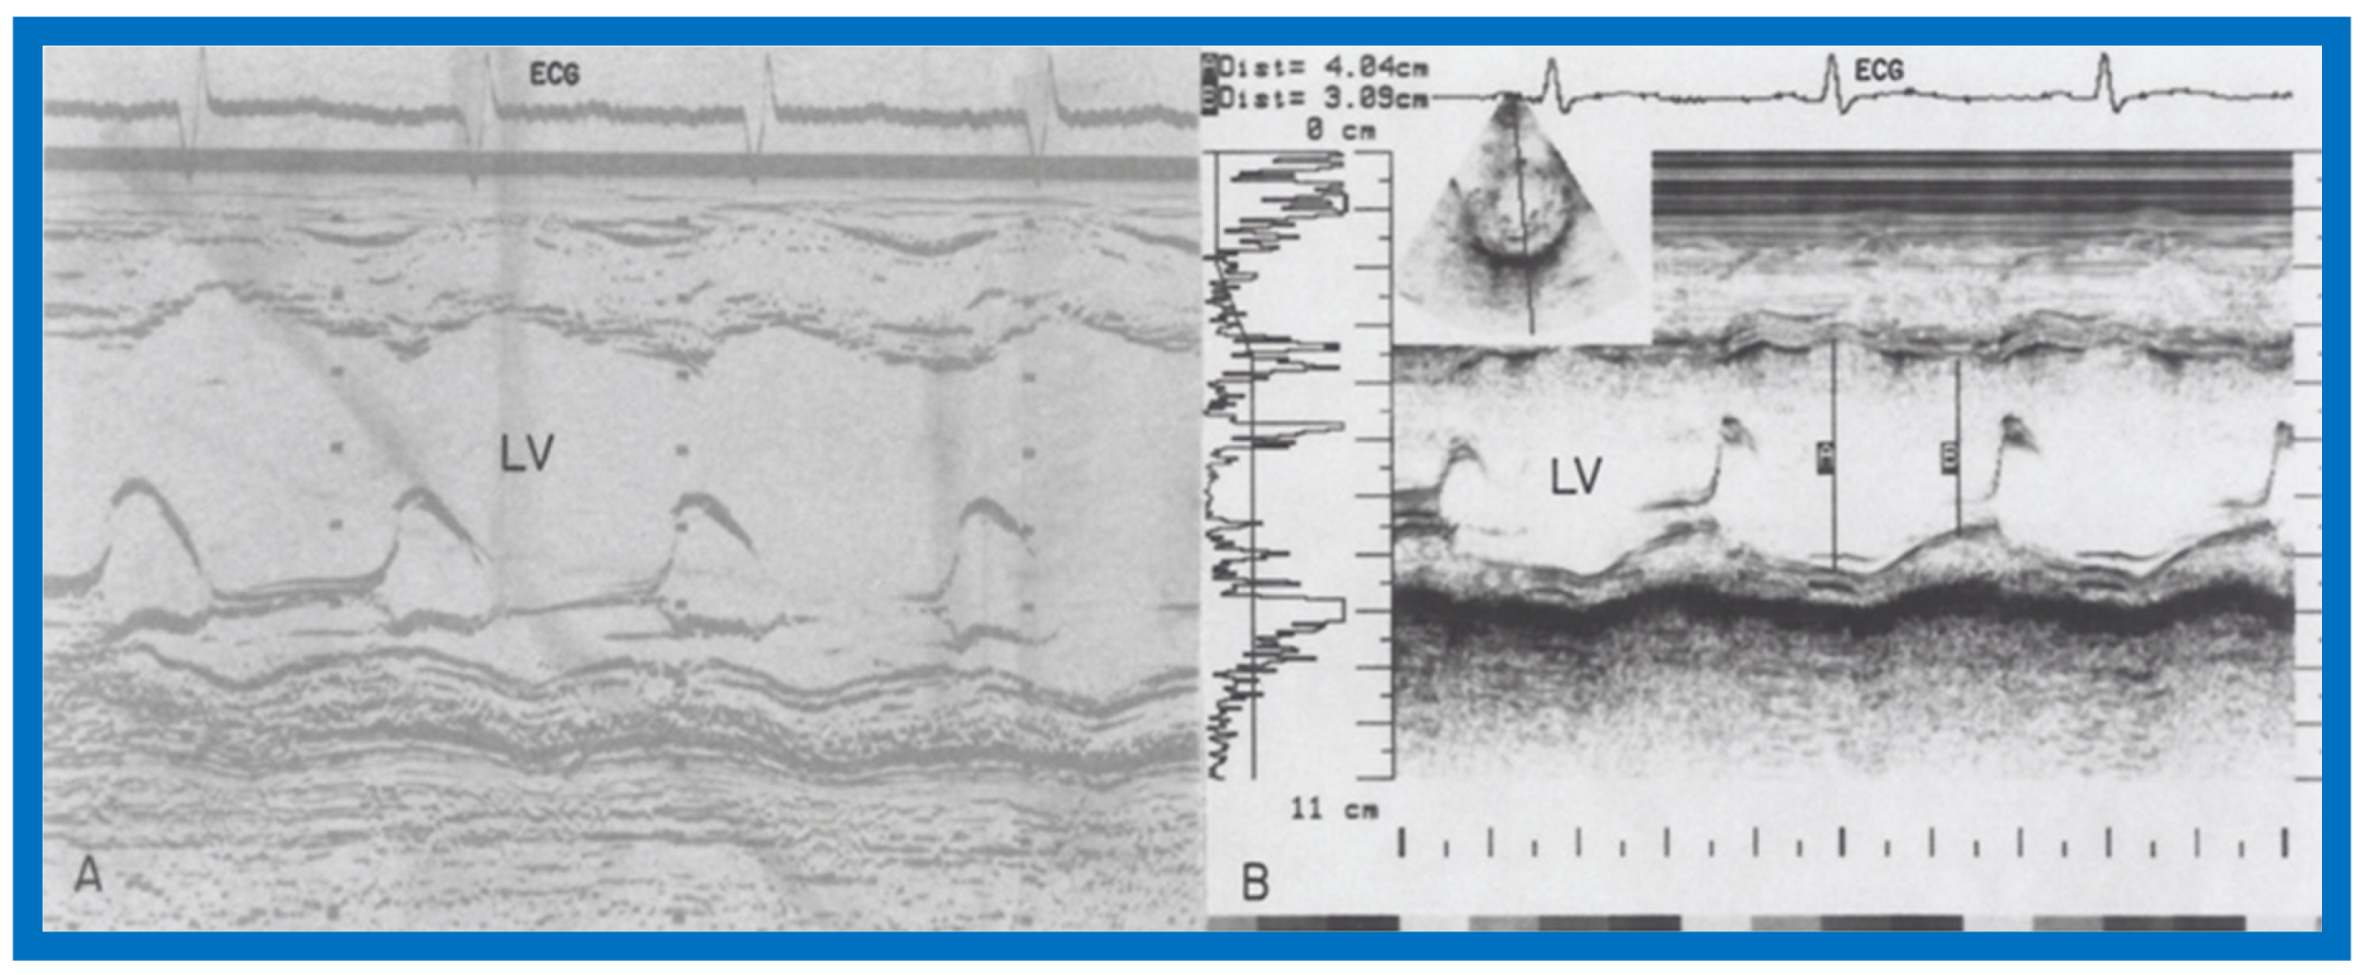

We presented the methods of measurements/calculations of systolic time intervals (Figure 11 and Figure 12), left ventricular volumes, LV shortening fraction (Figure 13), LV velocity of circumferential fiber shortening (Vcf), percent thickening of the LV posterior wall (Table 1) and their utility in the evaluation of LV function. This was followed by a discussion of diastolic function of the LV, other indices of LV function, LV function in aortic stenosis, LV function in LV volume overloading conditions and congestive cardiomyopathy. Then, newer methods (as of early 1980s) of assessing LV function by two-dimensional echocardiography, Doppler ultrasound-measured aortic blood flow velocity and radio-nuclide ejection fraction were briefed. The papers were concluded by outlining the value and limitations of noninvasive technology, as they were at that time [5,6].

Figure 13.

Selected M-mode recording from the parasternal short axis view of the left ventricle at the tips of the mitral valve illustrating measurements of left ventricular end-diastolic (LVEDD) and end-systolic (LVESD) dimensions to calculate shortening fraction (see Table 1). Reproduced from Rao P.S., Kulangara R.J. [5].